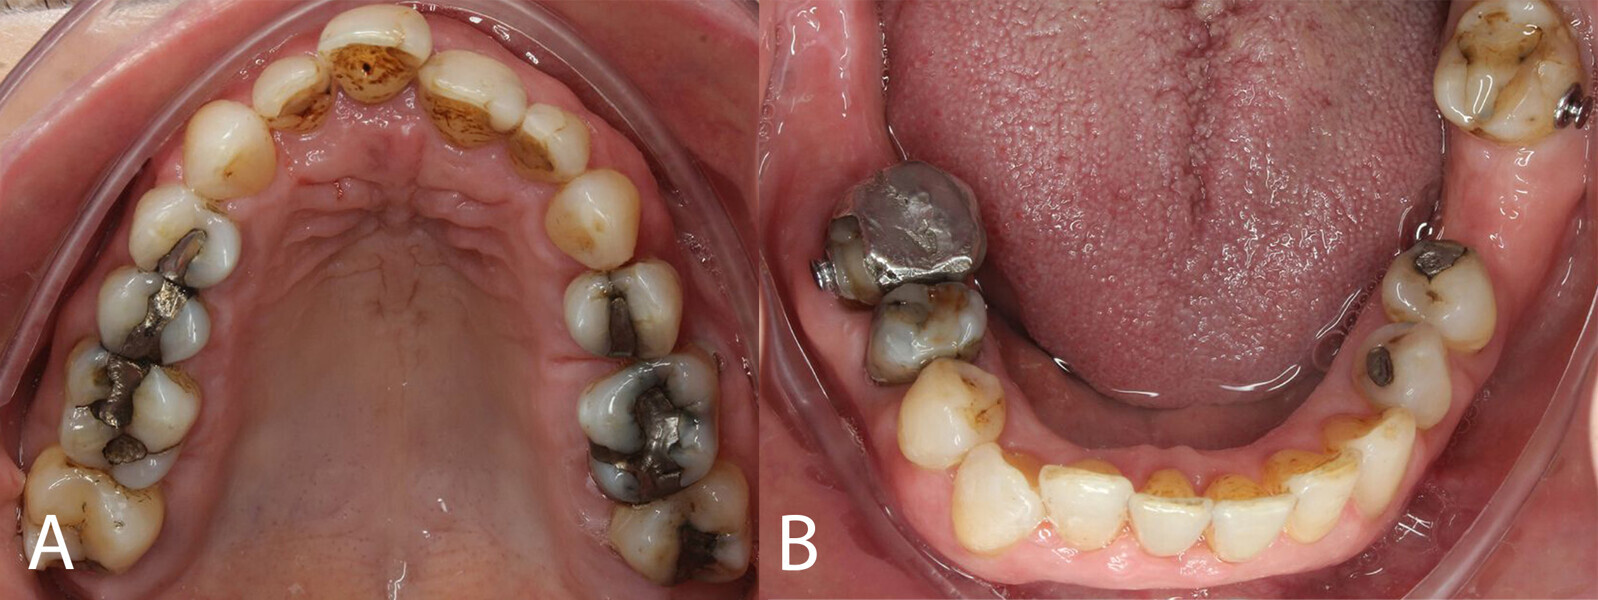

The periodontal treatment of an adult patient undergoing treatment with aligners is illustrated in demonstration of these points. Orthodontic planning considered the extra-oral photographs (Fig. 1) and intra-oral photographs (Figs. 2 & 3). Intra-oral scanning (Fig. 4) and radiographic documentation using panoramic radiographs and cephalometric radiographs (Figs. 5 & 6) were also carried out. From a periodontal perspective, periapical radiographs were recommended (Fig. 7), as this was an adult patient who smoked and showed clinical signs of advanced periodontal disease. Prior periodontal treatment was carried out (Fig. 8) to begin treatment with aligners (Fig. 9).

Fig. 8: After periodontal treatment.